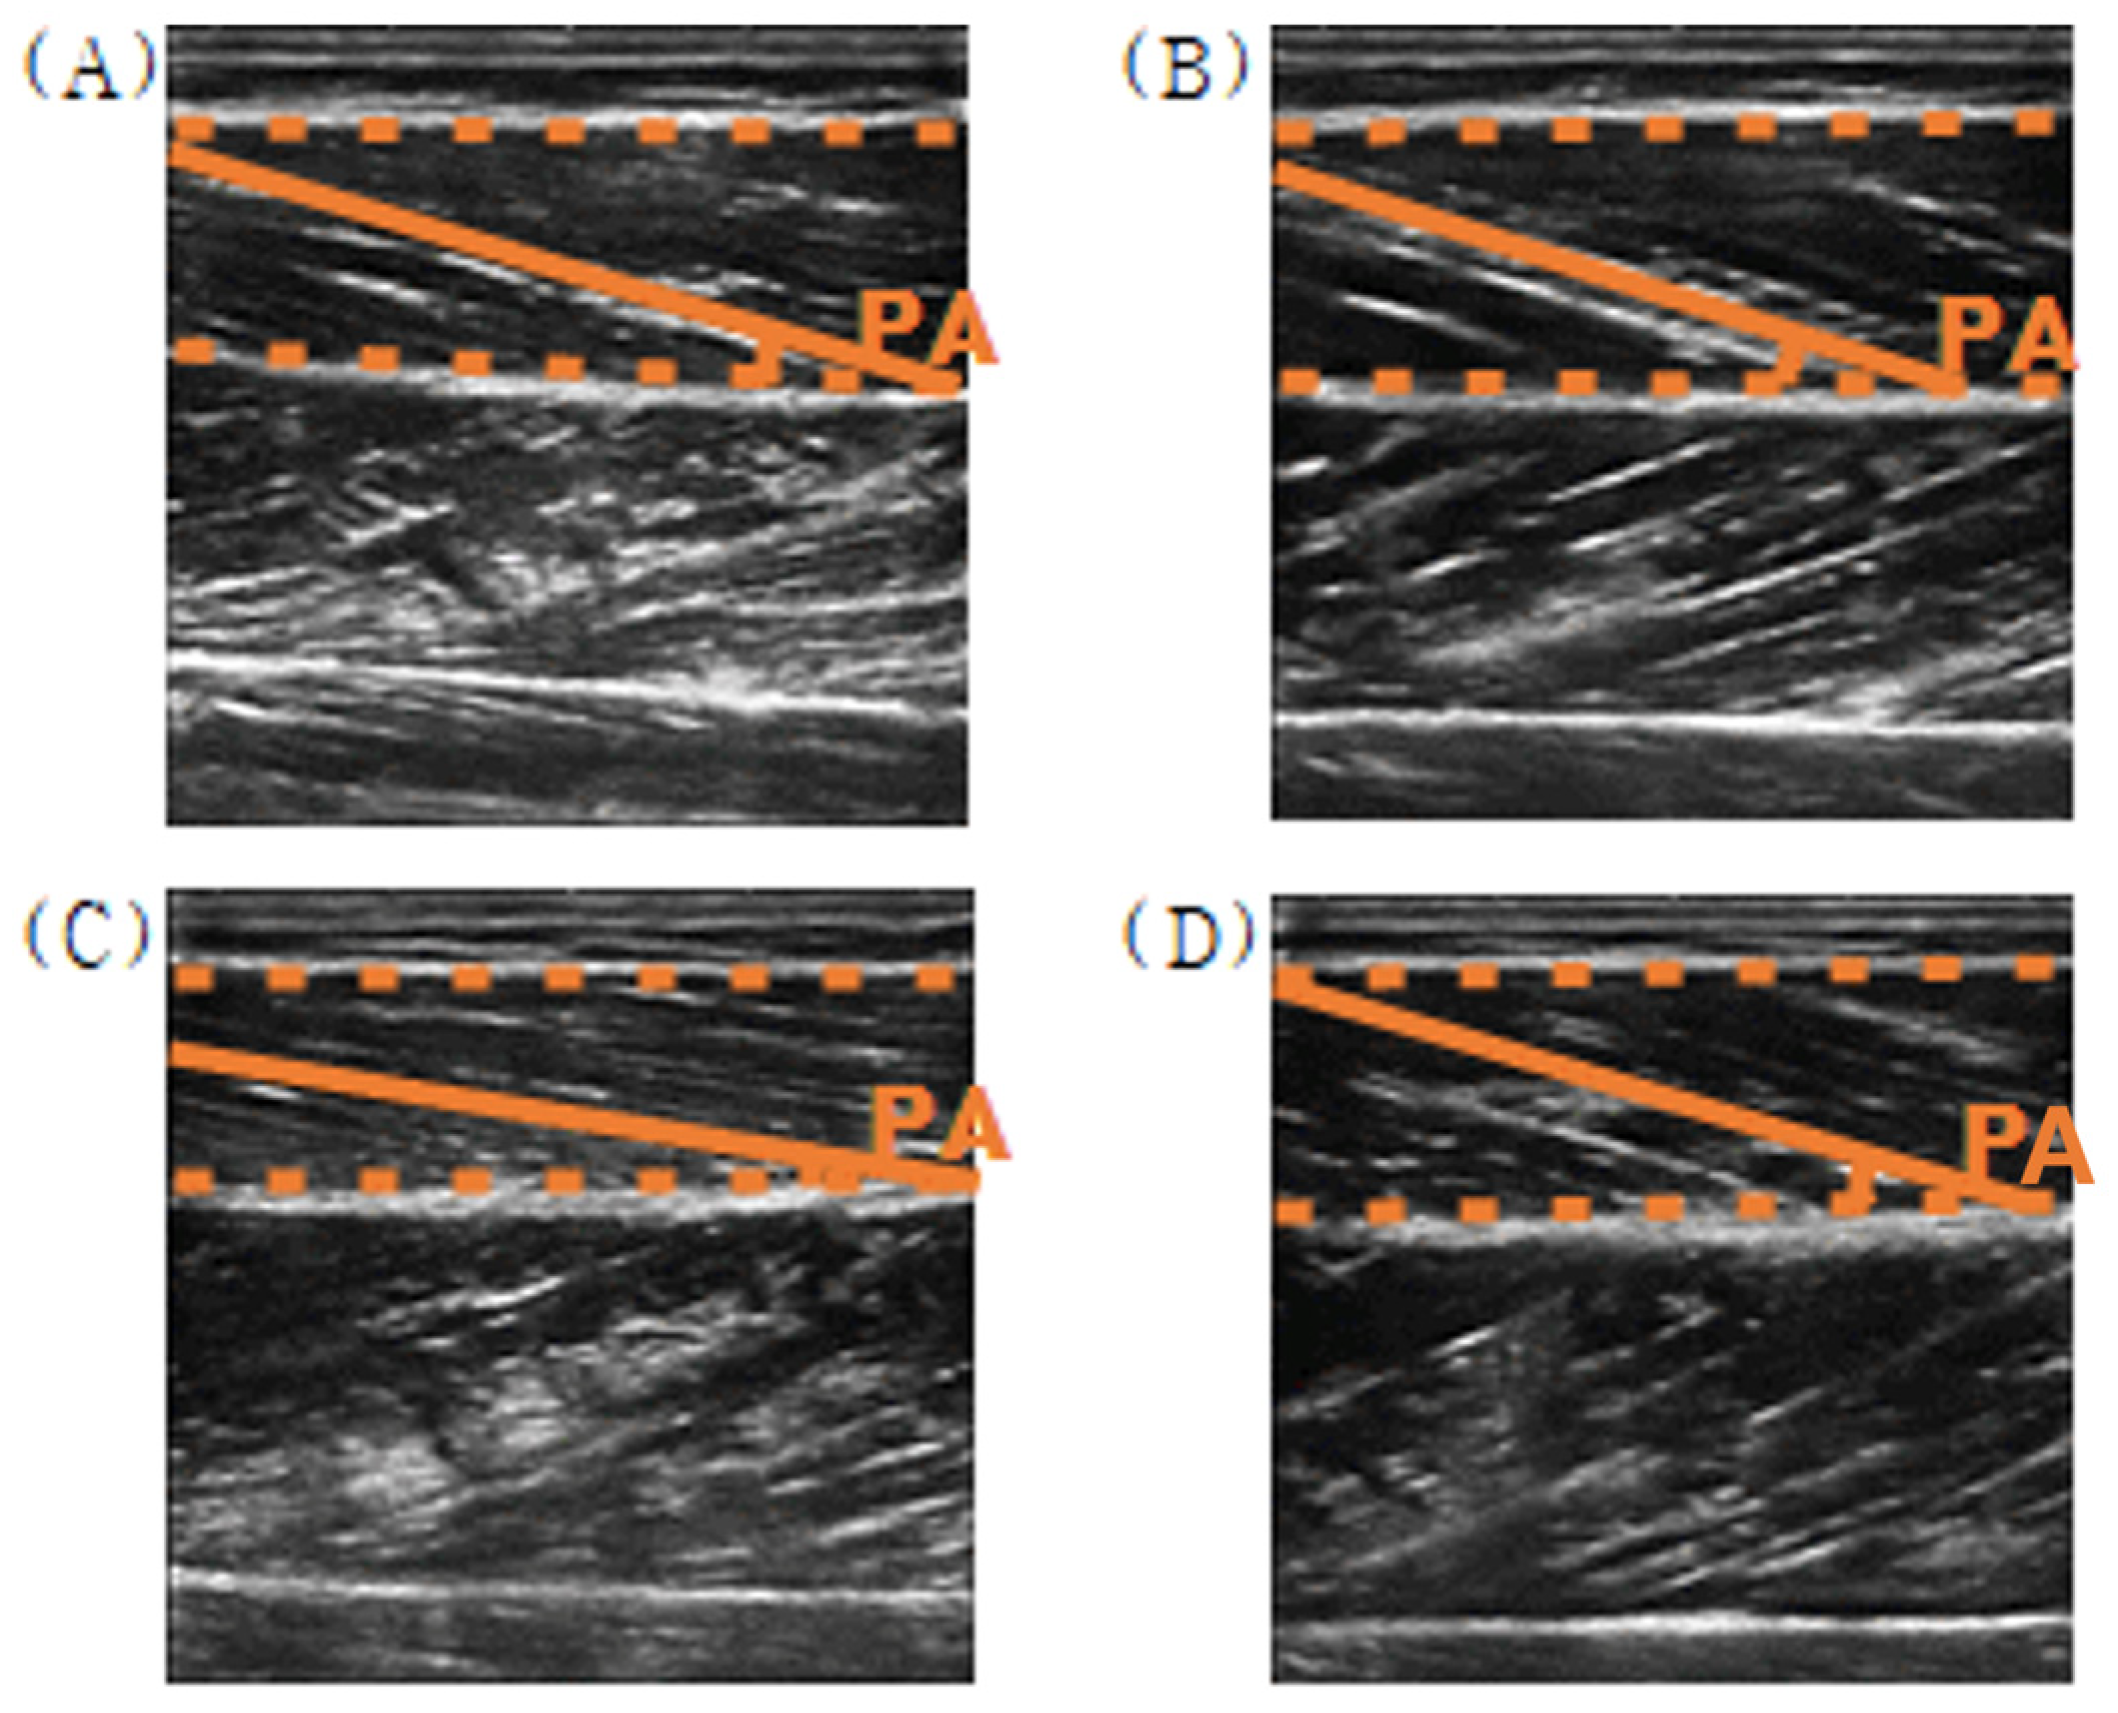

2.4.4. Pennation Angles of TA from the Ultrasound Images

| Pennation angle (deg) | VA | −0.22 | 2.75 | 3.18 | 1.96 |

| IA | −0.32 | 3.26 | 4.12 | 2.61 | |

| EA | 0.02 | 1.47 | 1.44 | 1.09 |